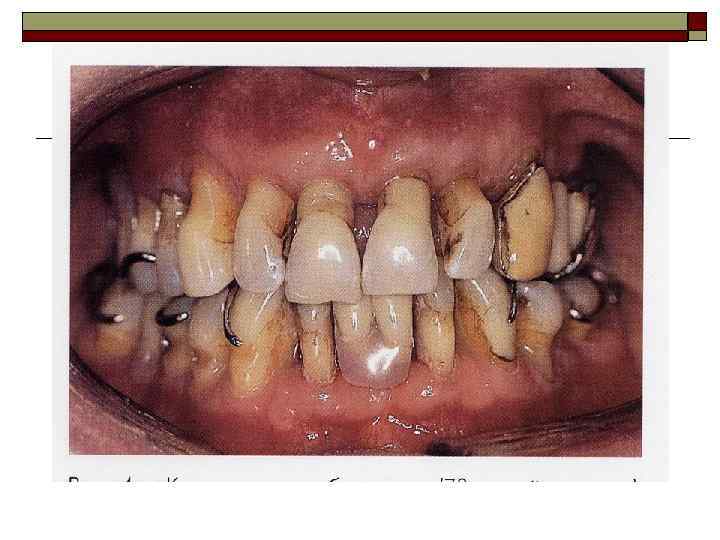

II. Пародонтит — воспаление тканей пародонта, характеризующееся прогрессирующей деструкцией периодонта и кости. Тяжесть: легкая, средняя, тяжелая. Течение: острое, хроническое, обострение (в том числе абсцедирование), ремиссия. Распространенность процесса: локализованный, генерализованный.

Представляют интерес классификации последних лет (Lisqarten, 1986; Watanabe, 1991 и др. ), особенно выделение быстротекущего пародонтита у взрослых (до 35 лет). I. Препубертатный пародонтит (7— 11 лет): • локализованная форма; • генерализованная форма. II. Ювенильный пародонтит (11— 21 год): • локализованная форма (ЛЮП); • генерализованная форма (ГЮП). III. Быстротекущий пародонтит взрослых (до 35 лет): • у лиц, имевших ЛЮП или ГЮП в анамнезе; • у лиц, не имевших ЛЮП или ГЮП в анамнезе. IV. Пародонтит взрослых (без ограничения возраста).

Перегрузка пародонта Деструктивно-воспалительные процессы могут наблюдаться при различных аномалиях прикуса (глубокий прикус, глубокое резцовое перекрытие, открытый, прогнатический, прогенический прикус и др. ) и положения зубов (скученность зубов); при ранней потере моляров и премоляров; после удаления большого количества зубов (постэкстракционные передвижения зубов); при неправильном определении показаний к мостовидному, особенно металлокерами-ческому, протезированию, неправильно сформированном преддверии полости рта; после хейло- и уранопластики; при бруксизме (ночное скрежетание зубами) и др.